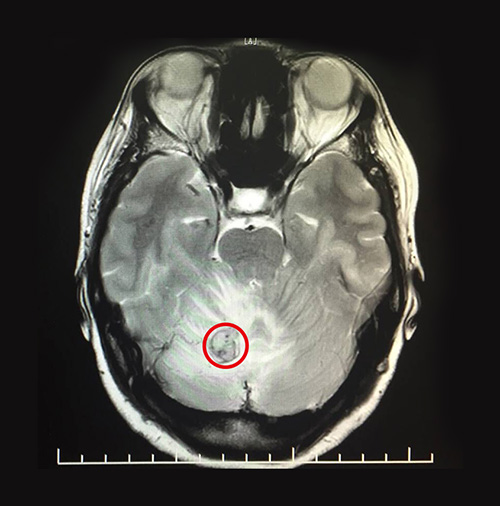

为了进一步明确病因,对患者又进行头颅MRI平扫+增强+PWI+DWI,结果显示:右侧小脑半球见一异常信号灶,边界清楚,T1WI为等高信号,T2WI等高信号,FLAIR呈略高信号,周围见大片状T1WI高水肿信号,DWI呈等低信号,病灶大小约15mm,增强扫描后可见强化。PWI示:右侧小脑半球病灶区脑组织CBV、CBF明显升高,MTT、TTP未见明显异常。

▲MRI影像显示,患者小脑有一个大小约15mmx15mm的肿瘤

最终孙阿姨被确诊为小脑肿瘤,结合病史(她曾于2015年3月进行左肾切除手术)考虑转移瘤。在诊断过程中,为了明确病因还进行了鉴别诊断,若是髓母细胞瘤,它多发于小脑蚓部,可伴小脑损害征,共济失调,病理检查可鉴别。若是脑膜瘤,它的表现主要为颅内压增高及局灶性症状及体征,脑膜瘤多发于蛛网膜粒分布部位,结合CT可鉴别。

手术开始,在显微镜的助力下,医术精湛的主任很快便精准的确定了患者的病灶区,整个手术操作过程他都一丝不苟。术中,可见其红色肿物,表面较光滑,血供丰富,充分切断肿物周围血供,最终完整切除了整个肿物,大小约15mmx15mmx15mm,历经3个小时,手术顺利完成。